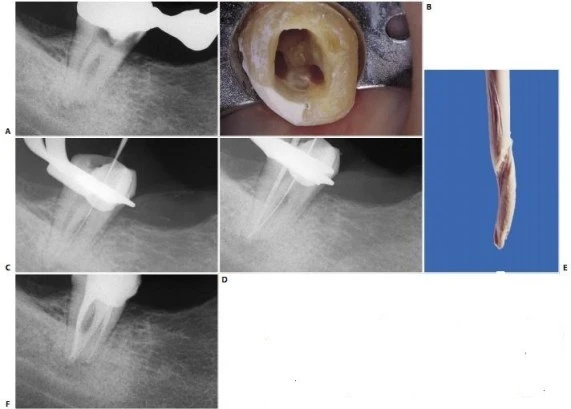

Đây là trường hợp giao nhau giữa ống tủy ngoài gần và ống tủy xa (hình 11.138) hoặc giữa ống tủy ngoài gần và ống tủy ngoài xa ở răng có hai ống tủy xa (hình 11.139), mặc dù hiếm gặp. Tại thời điểm thực hiện trám bít từng ống tủy riêng biệt, việc nén vật liệu ở ống tủy xa có thể đẩy chất trám ống tủy và gutta percha sang ống tủy gần ngoài qua chỗ thông vốn trước đó không được phát hiện. Điều này, bên cạnh những điều khác, xác nhận rằng với kỹ thuật phù hợp có thể sửa soạn hai ống tủy riêng biệt giao nhau mà không dẫn đến nguy cơ làm tắc bất kỳ ống tủy nào.

Sự thông nối giữa các ống tủy gần ngoài và ống tủy xa có thể được chẩn đoán từ giai đoạn sớm, đấy là trong quá trình làm sạch và tạo hình một trong hai ống tủy. Một khi một ống tủy được sửa soạn, một côn gutta percha được đặt vào và một dụng cụ nhỏ (ví dụ một trâm số 8) được đưa vào ống tủy khác mà chưa được sửa soạn trước đó. Nếu hai ống tủy thông nối với nhau, kiểm tra cẩn thận bề mặt của côn gutta percha sẽ thấy bộc lộ dấu vết để lại do trâm dùng trong ống tủy khác (hình 11.140).

Hình 11.138. Phim sau điều trị cho thấy ống tủy gần ngoài nhập vào ống tủy xa.

Hình 11.139. Răng cối lớn thứ hai hàm dưới với hai ống tủy xa và hai ống tủy gần. Ống xa ngoài đổ vào trong ống tủy gần ngoài. A. Phim trước điều trị. B. Xoang tủy. Lưu ý rằng hai miệng ống tủy ngoài, gần và xa rất gần nhau. C. Một dụng cụ được đưa vào ống tủy xa ngoài cho thấy có sự giao nhau với ống tủy gần ngoài. D. Hai dụng cụ nhỏ được đặt vào hai ống tủy nhằm xác nhận lại sự giao nhau này. E. Dấu bên trái của côn gutta percha, côn này vốn được đặt vào ống tủy xa ngoài, và trâm số #8 được đặt vào ống tủy gần ngoài. F. Thử côn. G. Phim sau điều trị. H. Hai năm sau.

Hình 11.140. Răng cối lớn thứ hai hàm dưới với sự giao nhau giữa ống tủy ngoài gần với ống tủy xa.

A. Phim trước điều trị. B. Xoang tủy: ống tủy ngoài gần có dạng hình elip, đối diện với ống tủy xa. C. Phim trong lúc điều trị: một dụng cụ được đưa vào ống tủy ngoài gần cho hình ảnh tương tự như thủng sàn tủy; thật ra, nó là dấu hiệu cho thấy có sự giao nhau giữa ống tủy này với ống tủy xa. D. Côn gutta percha được đặt vào ống tủy xa vốn đã được sửa soạn trước đó, một cây trâm nhỏ được đưa vào ống tủy gần ngoài chưa được sửa soạn. E. Dấu phía bên trái cây côn được gây ra bởi dụng cụ: đo chiều dài từ vị trí này đến đầu côn, ta có thể suy ra được khoảng cách giữa chỗ giao nhau và lỗ chóp. F.Phim sau điều trị.